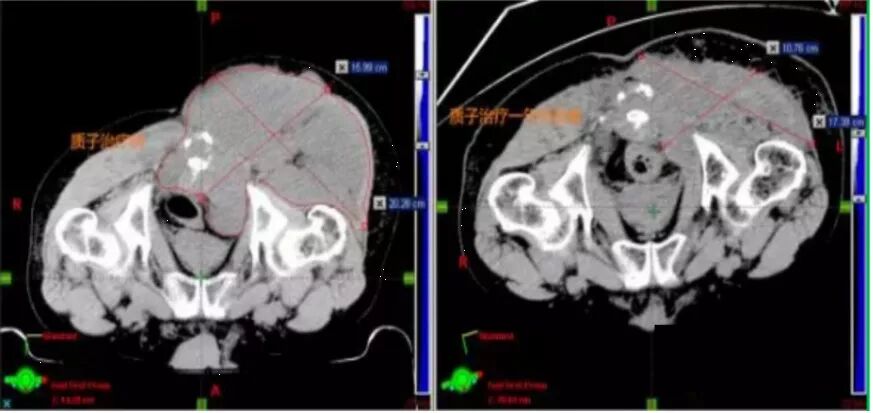

案 例 三

质子治疗脊索瘤一年后肿瘤体积缩小85%

患者:男,67岁

洗澡时无意中发现左侧臀部有一碗状肿物,局部皮肤无红、肿、热、痛及橘皮样改变。立即到医院就诊,行彩超发现左侧骶尾部肿物。进行左侧骶尾部肿瘤切除,术后病理为“脊索瘤”,术后辅助质子治疗。治疗后仅两个月,瘤体便开始缩小,治疗一年后,肿瘤体积缩小85%。

质子治疗一年后复查:肿瘤由原来的16×20.28cm缩小到10.76×17.39cm,局部纤维化明显,直肠恢复到正中,受压明显改善